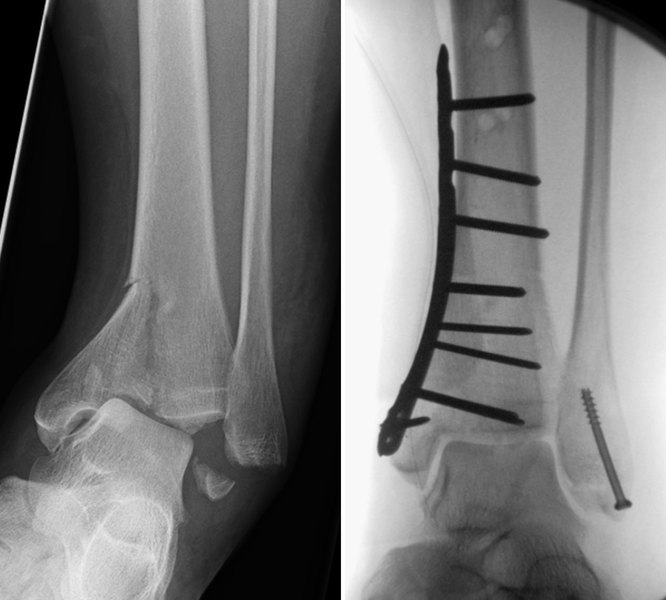

Zur operativen Behandlung von Knochenbrüchen, die auch die angrenzenden Gelenke betreffen (Handgelenk, Ellenbogengelenk, Schultergelenk, Hüftgelenk, Kniegelenk, Sprunggelenke), stehen moderne Osteosyntheseverfahren (sog. winkelstabile Osteosyntheseplatten) zur Verfügung.

Knochenbrüche des Aussen- und Innenknöchels sowie der Gelenkfläche des Schienbeins werden mit Platten-/Schraubensystemen versorgt. Ebenso die seltener auftretenden Knochenbrüche des Sprungbeins und des Fersenbeins.